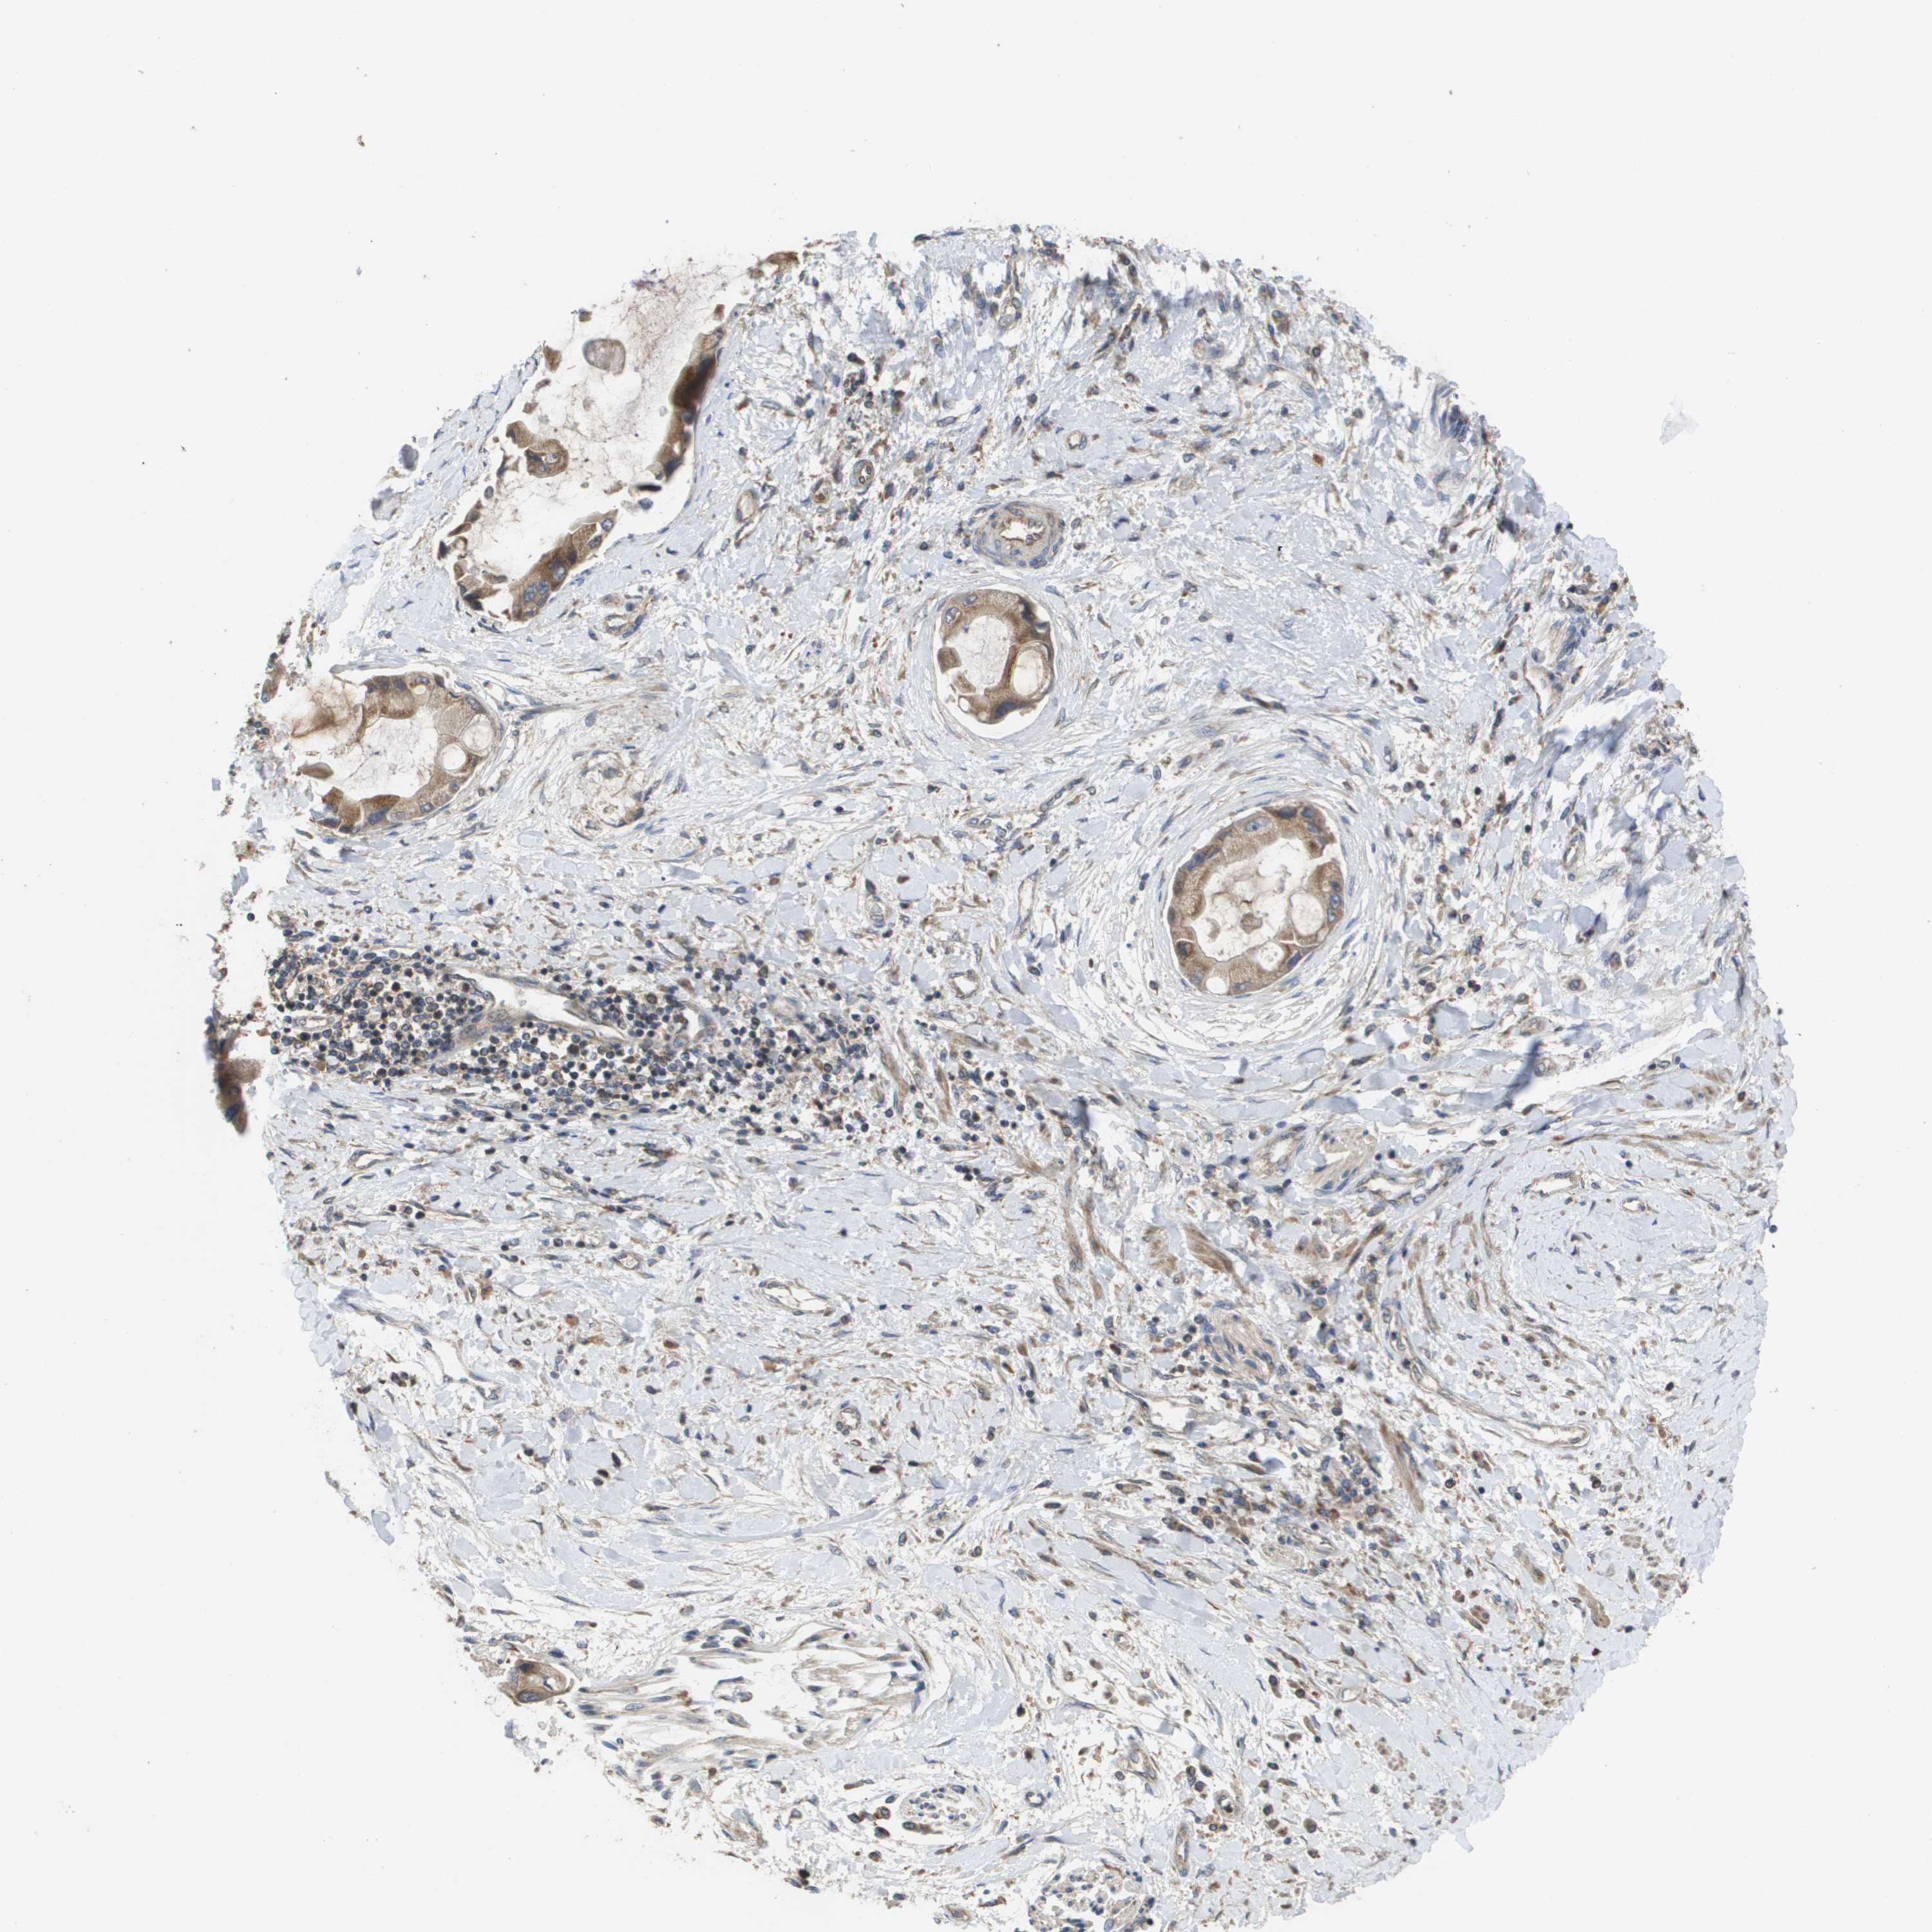

LIVER CANCER - Protein expressioni

A mouse-over function shows sample information and annotation data. Click on an image to view it in a full screen mode. Samples can be filtered based on level of antibody staining by selecting one or several of the following categories: high, medium, low and not detected. The assay and annotation is described here.

Note that samples used for immunohistochemistry by the Human Protein Atlas do not correspond to samples in the TCGA dataset.

Antibody stainingi

Antibody staining in the annotated cell types in the current human tissue is reported as not detected, low, medium, or high, based on conventional immunohistochemistry profiling in selected tissues. This score is based on the combination of the staining intensity and fraction of stained cells.

Each image is clickable and will lead to virtual microscopy that enables deeper exploration of all samples and also displays staining intensity scores, fraction scores and subcellular localization as well as patient and tissue information for each sample.

Antibody CAB017036

Staining

High

Medium

Low

Not detected

Intensity

Strong

Moderate

Weak

Negative

Quantity

>75%

75%-25%

<25%

None

Location

Nuclear

Cytoplasmic/membranous

Cytoplasmic/membranous,nuclear

Cholangiocarcinoma

Carcinoma, Hepatocellular, NOS